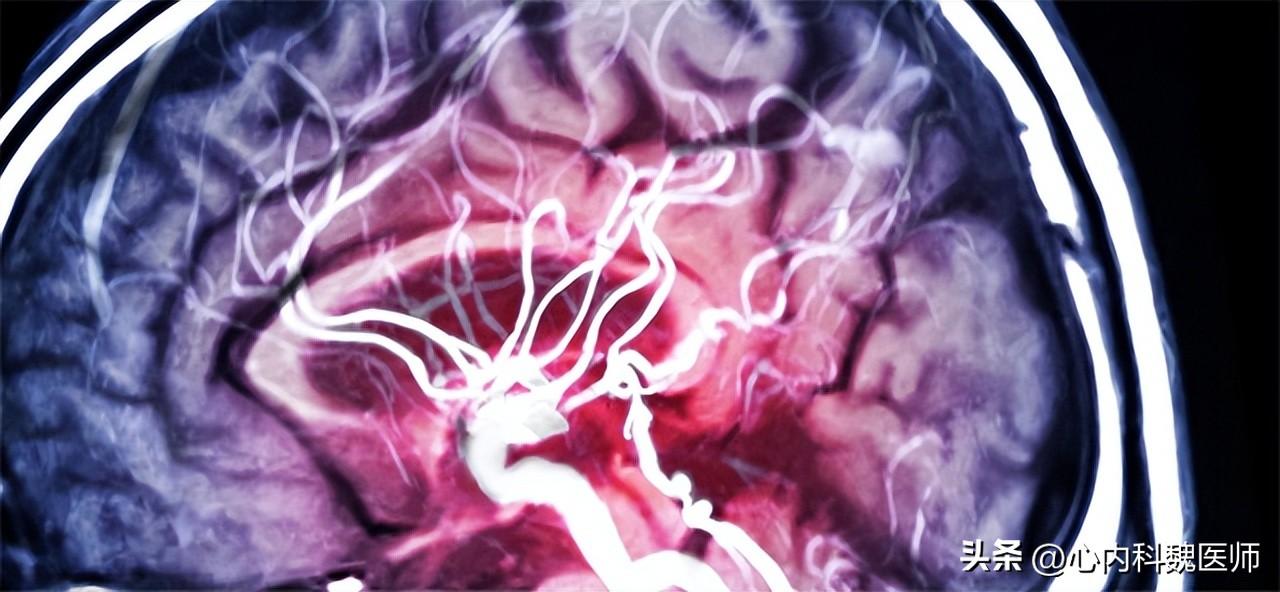

(脑动脉破裂瞬间)

四川大学华西医院神经外科副教授 王朝华医生 曾向小康妹儿介绍过:脑动脉瘤(颅内动脉瘤)是因为各种因素造成的脑内动脉血管壁出现向外膨出的局部囊性扩张,形似长在血管上的“瘤”,但它并不是人们常识性认为的实质性“肿瘤”。

脑动脉瘤就像车胎磨薄之后的局部鼓包,鼓包处的车胎壁比其他地方都薄,这样车辆在行驶过程,一不小心就会爆胎,而血管的“爆胎”就会造成颅内大出血,也就是通常所说的脑出血中的一种。

因此,脑动脉瘤被称为“不定时炸弹”。